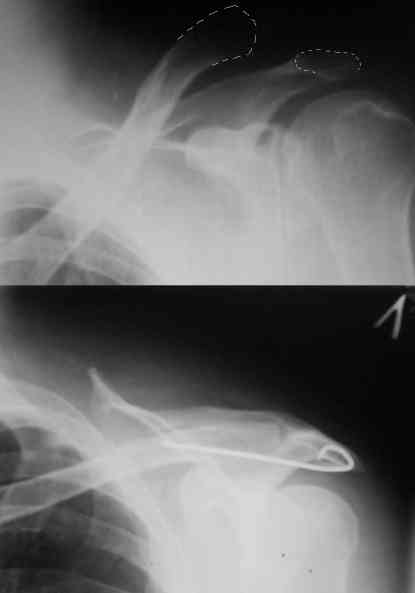

Re: Вывих акромиального конца ключицы

Внешний вид больного (травма: 09.10.2007, операция: 11.10.2007) Ориентиры доступа: овальный – пальпируемый акромиальный конец ключицы, линейный – операционный разрез

Введение крючка в подготовленный канал Дистальная часть крючка подведена под акромион и фиксирована на нем путем загибания (вывих ключицы устранен)